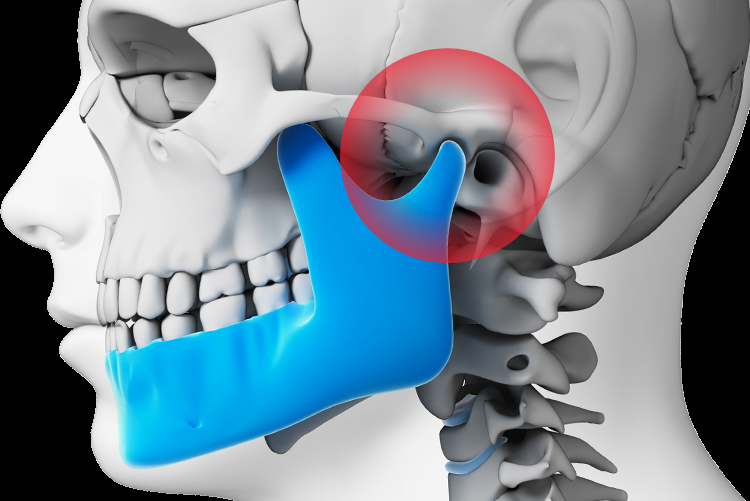

TMJ (Jaw Joint) Therapy

Relief from jaw pain, headaches, and bite-related discomfort.